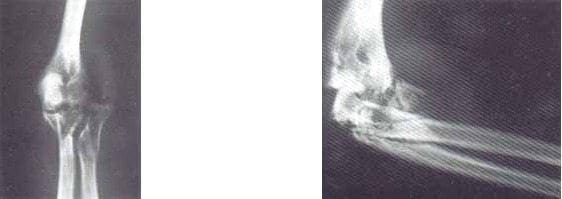

Paciente de 25 años de edad, sexo masculino, quien sufre herida por proyectil de arma de fuego de alta velocidad en el codo izquierdo, presentando fractura conminuta de la cúpula radial, fractura conminuta de cúbito proximal, fractura conminuta de cóndilo humeral lateral, lesión del complejo ligamentario colateral lateral y pérdida del 30% de la superficie articular del olécranon (figuras 4 y 5).

Figs. 4 y 5 Radiografía AP y lateral de codo con fractura conminuta cúpula radial,

fractura conminuta de cúbito proximal, fractura conminuta cóndito humeral lateral